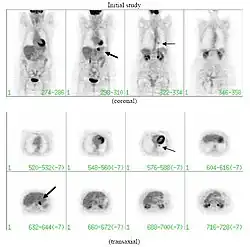

FDG-PET study of a 71-year-old woman with a solitary pulmonary nodule (thin arrow) in the left lower lobe near the heart. The scan also revealed abnormal increased activity at the gastro-esophageal junction (thick arrow). The final diagnosis was non-Hodgkin lymphoma at both sites.

If there is an intermediate risk of malignancy, further imaging with positron emission tomography (PET scan) is appropriate (if available). It can be done simultaneously as a CT scan in the form of PET-CT. Around 95% of patients with a malignant nodule will have an abnormal PET scan, while around 78% of patients with a benign nodule will look normal on PET (this is the test sensitivity and specificity).[15] Thus, an abnormal PET scan will reliably pick up cancer, but several other types of nodules (inflammatory or infectious, for example) will also show up on a PET scan. If the nodule has a diameter of less than one centimeter, PET scans are often avoided because of an increased risk of falsely normal results.[15][16][17] Cancerous lesions usually have a high metabolism on PET, as demonstrated by their high uptake of FDG (a radioactive sugar).